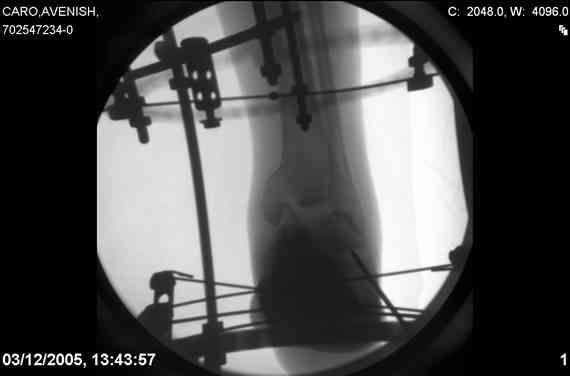

ya by popytalsya sobrat talus anatomichno,seichas pozdno operirovat iz za oteka,po etomy distrakziya apparatom budet optmalna.Posyalu vam podobyai moi sluchai.

14 years old girl

Fall from height ( 3rd floor)